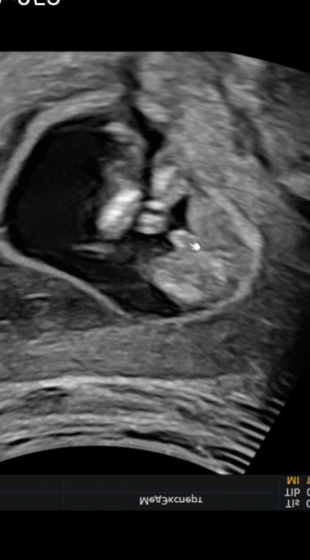

14.2н?была я значит вчера на узи, наша девочка неожиданно стало мальчиком ?Хотя на узи даже половые губы показывали? в общем передумала? отрос пысюн! И здесь вопрос девочки, ну мальчик же?? я конечно была уверенна что пол не 100% в 13.5 недель, ну что то я как то уже настроилась ? не расстраиваюсь ничуть ☺️ главное что бы все хорошо?

Пацан пацан растёт 999%

Ну тут конечно мужчина растет??

500% мальчик, я то знаю))) мне 2 раза на первых узи говорили, что выросло то выросло и не ошиблись ))))

Мальчик точно?